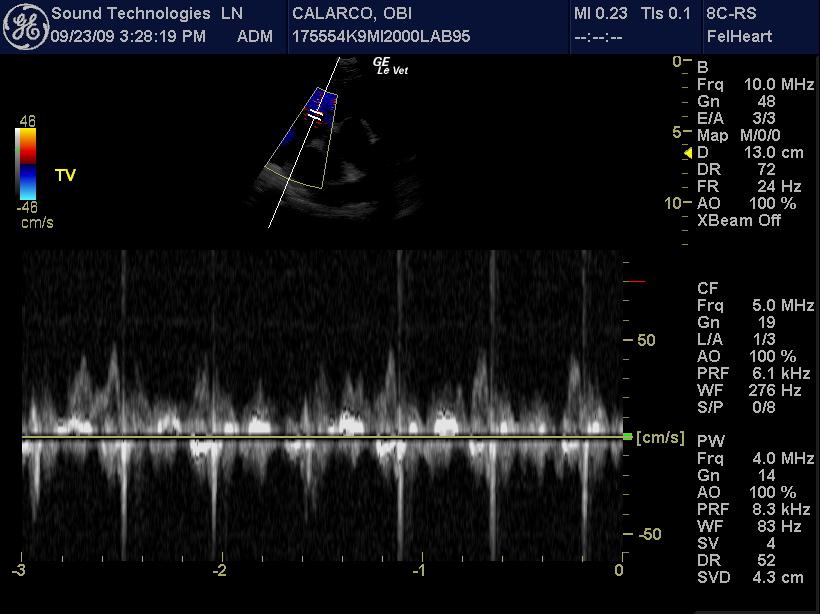

An 11-year-old MN Labrador retriever was prestented for excercise intolerance, lethargy, depression, vomiting and diarrhea. The physical exam was unremarkable other than a grade 2 left sided heart mumur at the heart base and irregular heart beat with pulse deficits. CBC, CHEM, UA, and acth stim were all normal.